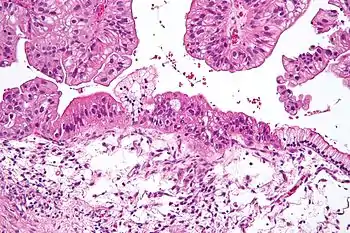

Micrograph of a mucinous ovarian carcinoma stained by H&E.

Mucinous tumors include mucinous adenocarcinoma and mucinous cystadenocarcinoma.[20]

Mucinous adenocarcinoma

Mucinous adenocarcinomas make up 5–10% of epithelial ovarian cancers. Histologically, they are similar to intestinal or cervical adenocarcinomas and are often actually metastases of appendiceal or colon cancers. Advanced mucinous adenocarcinomas have a poor prognosis, generally worse than serous tumors, and are often resistant to platinum chemotherapy, though they are rare.[20]